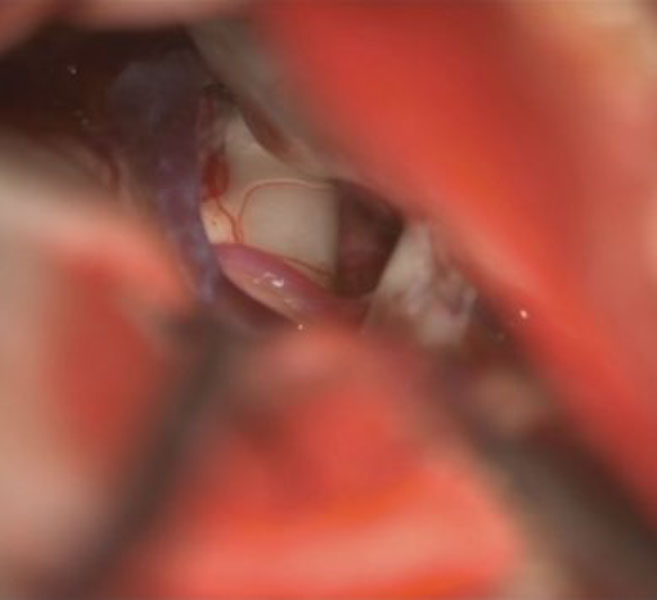

症例 '26年4月

No.

588

手術医師

手術年月

年齢

病名

術式

手術前

減圧前

減圧後

手術後

京都府の病院

'26年4月

40代

右三叉神経痛

(顔面の痛みをとること)

術後血管撮影